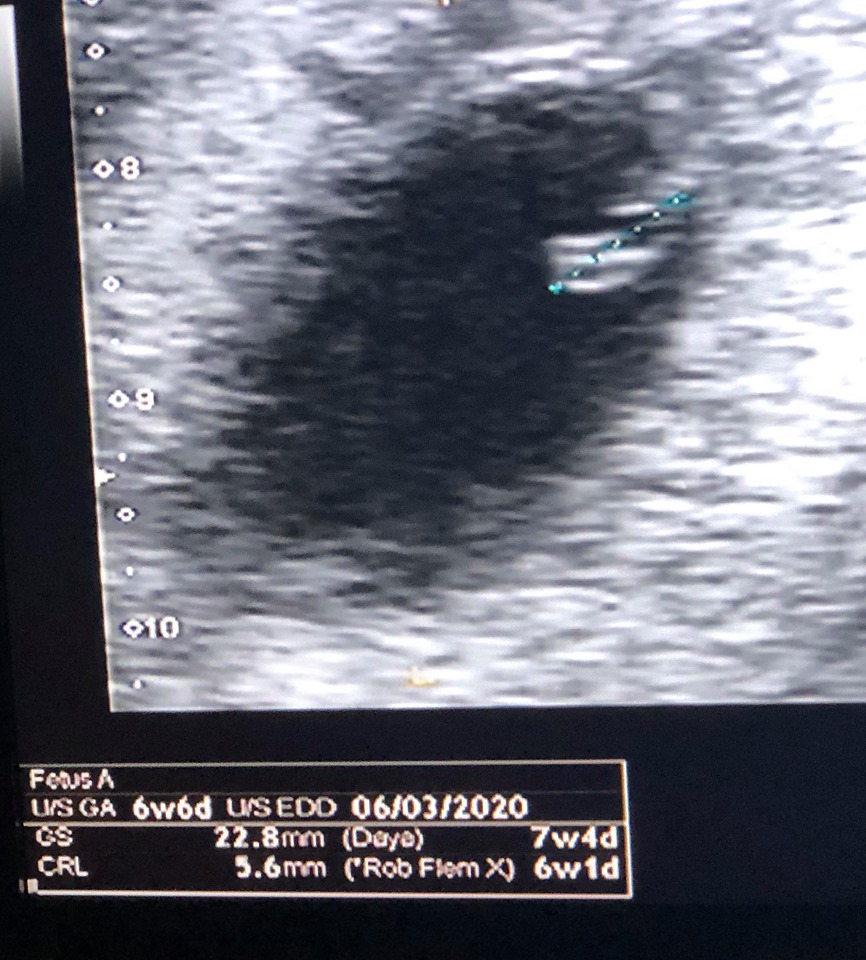

I was sent to EPU as was being very sick . By my dates I was 7 weeks , by theirs I was 6 weeks . The sonographers explained that the earlier the scan the more accurate as the embryo has very standard development . I had one embryo with fetal pole and heartbeat and one blighted ovum .

I am 7 weeks pregnant with my first baby, my GP sent me for a scan at when we predicted I would be 6 weeks for a dating scan . When I went to the ultrasonographer, she said that I was 5 weeks 4 days . At this time she did an external and internal ultrasound . DH and I could see a heart beat on the screen .